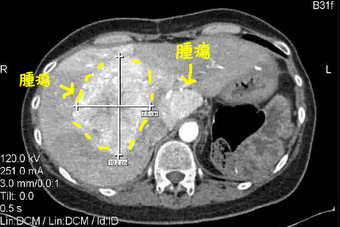

それがこちら(↓)は、2年前、私がバーゼルに行く直前のCT画像です。

輪切りにされた肝臓の連続写真をクリックしていると、現れました! ど真ん中の一番でっかい腫瘍。

「定規」で計ってみたら、10.2 X 7.6 センチ。当時のCTレポートとほぼピッタシの大きさ。

BINGO!!

ちなみに、昨日先生と一緒に見たCT(今月初め)は、このくらいになってて、計ると5センチ程でした。これだけ縮んでるのを見ると、PRRTの効果はやはり凄いですね。

それがこちら(↓)は、2年前、私がバーゼルに行く直前のCT画像です。

輪切りにされた肝臓の連続写真をクリックしていると、現れました! ど真ん中の一番でっかい腫瘍。

「定規」で計ってみたら、10.2 X 7.6 センチ。当時のCTレポートとほぼピッタシの大きさ。

BINGO!!

ちなみに、昨日先生と一緒に見たCT(今月初め)は、このくらいになってて、計ると5センチ程でした。これだけ縮んでるのを見ると、PRRTの効果はやはり凄いですね。